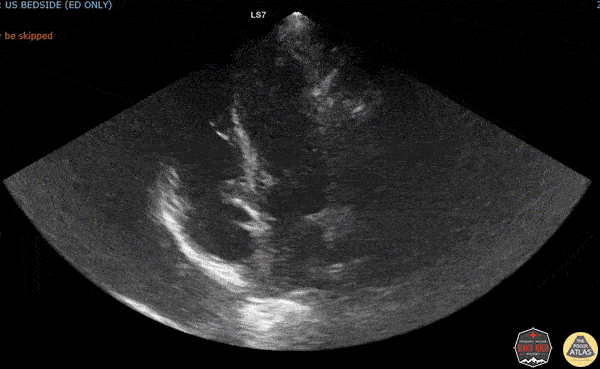

A careful look will show something extra on the mitral valve. Dr. Sarah Banks, Dr. Molly Thiessen - Denver Health Emergency Medicine